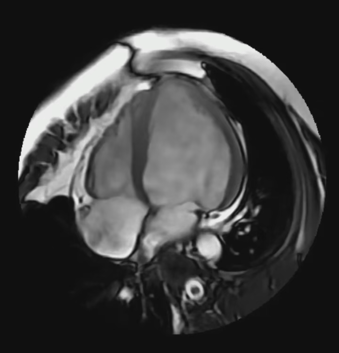

使用Cine图像进行心功能分析,LVEF = 43%。低于正常值50 ~70%。然并卵,B超不能测量心功能么?2.2 脂肪抑制黑血DIR FSE

电影序列提示壁薄处,心肌厚度明显变薄,且其中混杂低信号。什么原因导致,出血成分,脂肪沉积,纤维成分?心室内混杂血流信号,这符合患者心衰症状;心衰患者,心室内的血液流动性变差,类似于附壁的慢血流,慢血流相当于静止的水,所以T2fs呈高信号。2.3 心肌T1 MAPPING